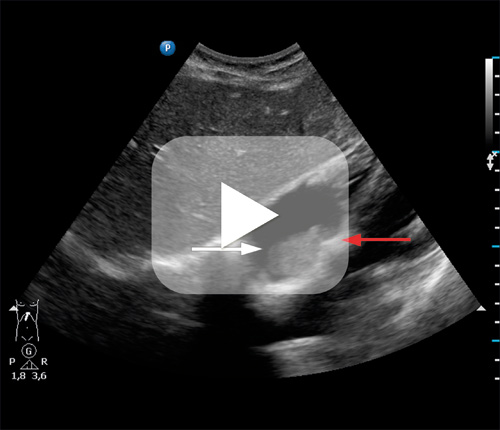

Det var normale funn ved auskultasjon av hjerte og lunger og normal puls, normalt blodtrykk, surstoffmetning og EKG. Ettersom fastlegen hadde ultralydutstyr, undersøkte han henne med en abdominal probe subkostalt. Han oppdaget da en moderat ekkorik tumor (hvit pil) i høyre atrium på 2 × 3 cm som var tilheftet septum (rød pil). Fastlegen kontaktet kardiolog ved lokalsykehuset med spørsmål om dette kunne være en trombe eller et myksom. Kardiologen undersøkte pasienten samme dag, og tumor ble bekreftet med ekkokardiografi og senere med MR cor, som ga mistanke om myksom eller sarkom. Pasienten ble operert ved universitetssykehus en måned senere, og diagnosen myksom ble bekreftet histologisk.